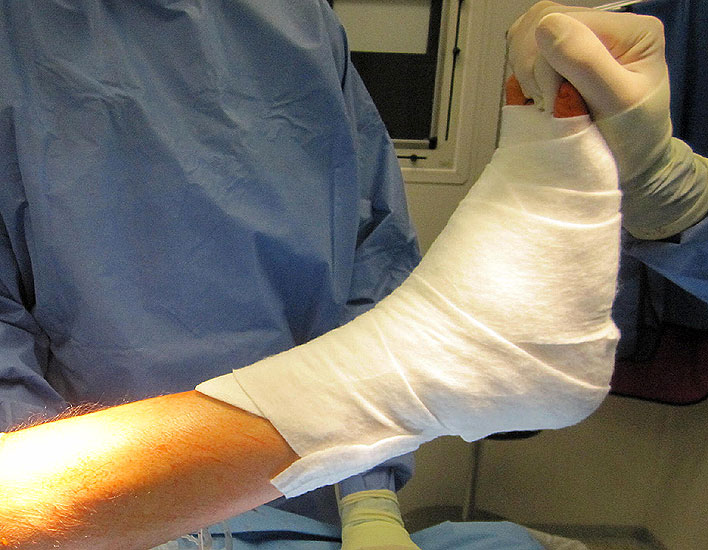

• 1. Verbandswechsel am 2. postoperativen Tag mit Drainagenentfernung.

• 1.-6. Woche Ruhigstellung in einer dorsalen Unterschenkel-Kunststoffschiene, nach Abschwellung am Tag Ruhigstellung in einem Unterschenkelwalker, zur Nacht in der Schiene; bei knöchernen Zusatzeingriffen bzw. Sehnentransfers weitere Ruhigstellung im Unterschenkelwalker am Tag bis Ende der 12. Woche; aktiver Hinweis auf einen vollständigen Fersenkontakt im Walker zur Vermeidung einer Spitzfußkontraktur.